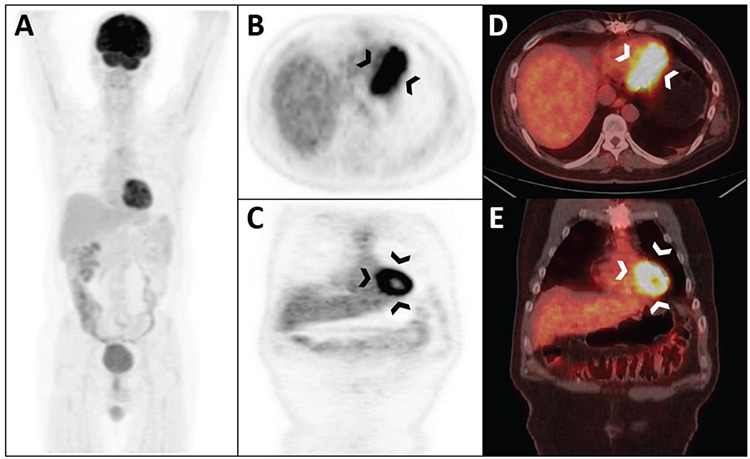

原始神经外胚层肿瘤(PNET)是小圆形细胞癌家族中罕见的侵袭性肿瘤。一般来说,PNET 主要分为两类:中枢神经系统 PNET 和周围神经系统 PNET。在此,我们报告了利用 18F- 氟脱氧葡萄糖(18F-FDG)正电子发射断层扫描/计算机断层扫描(PET/CT)成像对一例罕见的孤立性心脏 PNET 进行治疗反应评估的结果。鉴于通常可观察到生理性心脏 FDG 摄取,评估心肌中的 FDG 受体病变对 FDG PET/CT 来说是一项挑战。本病例的意义在于该疾病的罕见性和 FDG PET/CT 成像部位的挑战性。

Primitive neuroectodermal tumors (PNETs) are rare and aggressive members of the small round cell carcinoma family. Generally, PNETs are classified into two main groups: PNETs of the central nervous system and PNETs of the peripheral nervous system. Herein, we report the therapy response assessment of a rare case of isolated cardiac PNET using 18F-fluorodeoxyglucose (18F-FDG) positron emission tomography/computed tomography (PET/CT) imaging. Given that physiological cardiac FDG uptake is typically observed, assessing FDG avid lesions in the myocardium presents a challenge for FDG PET/CT. This case holds significance because of the rarity of the disease and the challenging nature of the site for FDG PET/CT imaging.